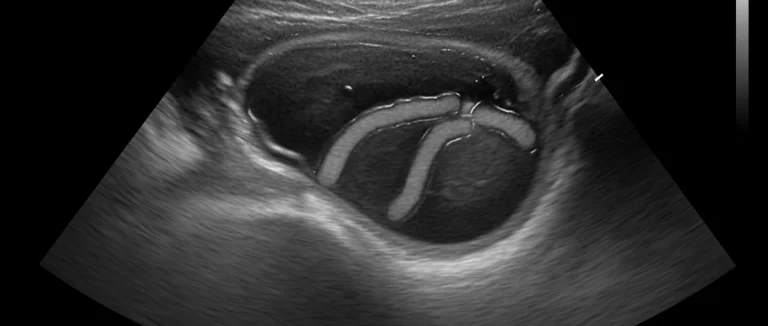

| УЗИ (ультразвуковое исследование) | Изображение структуры сухожилия, наличие жидкости в оболочке. |

В Лив Хоспитал применяется современное оборудование, позволяющее получить чёткие изображения даже при небольших изменениях. Это особенно важно при подозрении на хронический тендинит, где визуализация микроскопических разрывов определяет необходимость хирургического вмешательства.

Врач начинает с подробного клинического осмотра, оценивая локализацию боли, степень отёка и подвижность сустава. УЗИ позволяет увидеть структуру сухожилия, наличие жидкости в оболочке и степень воспаления в реальном времени. Магнитно‑резонансная томография (МРТ) даёт высокую детализацию мягких тканей, выявляя микротрещины и степень фиброза. Эластография измеряет упругость тканей, помогая отличить воспалительный отёк от хронического фиброзного изменения. В Лив Хоспитал используют современное оборудование, обеспечивая точную визуализацию даже при небольших изменениях.